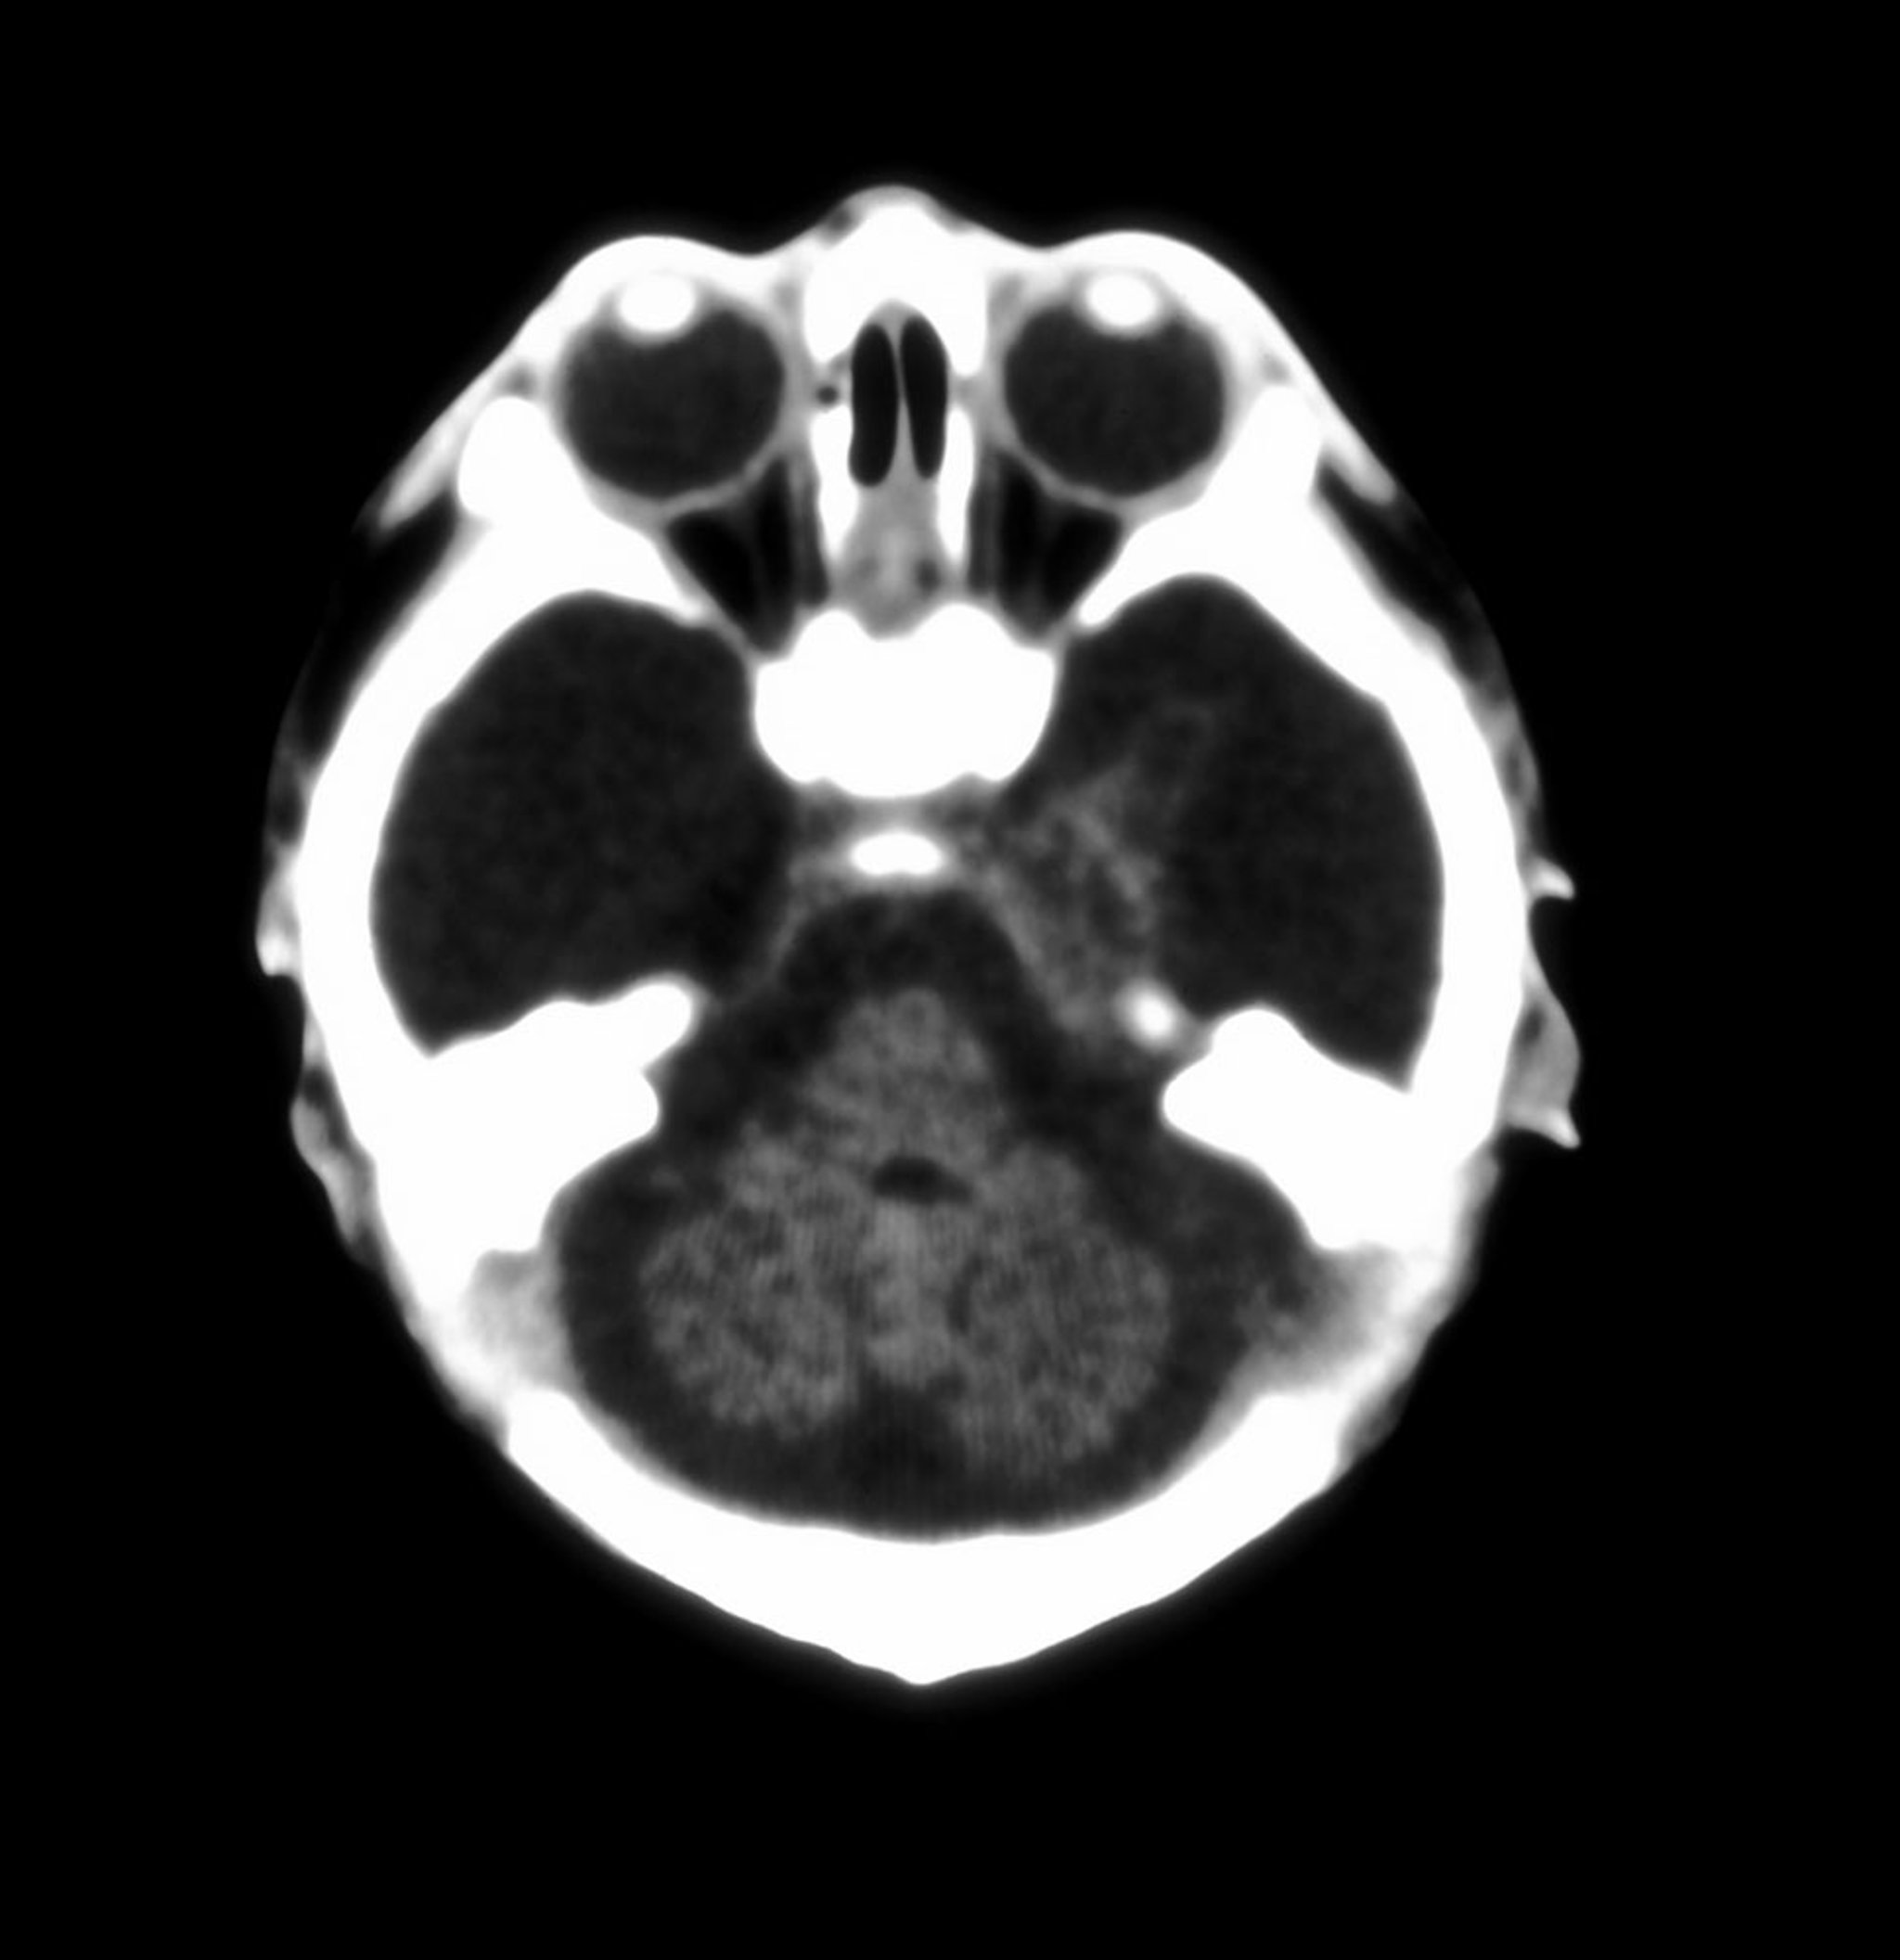

Hydranencephaly

This axial CT image of the brain in a neonate shows almost total absence of the cerebral hemispheres.